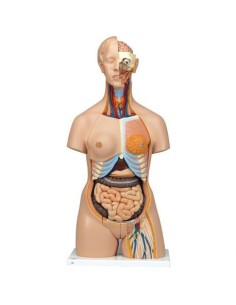

Scopri il Mondo dell’Anatomia con Modelli anatomici di Precisione

Modelli Anatomici Dettagliati per Ogni Necessità

Dal cranio in 22 parti con incastri magnetici ai modelli di colonna vertebrale, da quelli di articolazioni a quelli di cuore, ogni pezzo della nostra collezione è progettato per un’immersione totale nello studio dell’anatomia umana. I nostri modelli, realizzati tramite scansioni di ossa vere, garantiscono un’esperienza tattile autentica e una fedeltà di peso quasi identica agli originali.

Strumenti Didattici Innovativi per l’Educazione e la Pratica Medica

Essenziali per studenti e professionisti, i nostri modelli anatomici sono strumenti didattici che permettono di osservare le strutture anatomiche con precisione, eliminando la necessità di dissezioni o studi invasivi. Sono inoltre utili per spiegare ai pazienti le patologie, rendendo la comunicazione più efficace e risparmiando tempo prezioso.